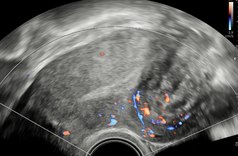

b) diagnostikou a léčbou endometriózy, neplodnosti a chronických pánevních bolestí

• Diagnostika a léčba endometriózy